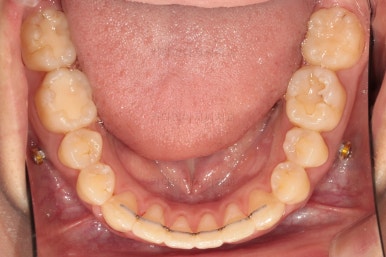

치열의 고른 느낌 좋고요.

덧니, 교합, 중앙선 등 모든게 좋아졌네요.

교합, 맞물림, 중앙선, 덧니, 입매, 앞니위치 및 각도 모든게 잘 마무리 되었습니다.

비발치로 오히려 입이 들어가게(악궁확장이나 치간삭제(공간확보의 목적) 없이도) 할 수 있었던 부산치아교정치과 좋은 치료였습니다.